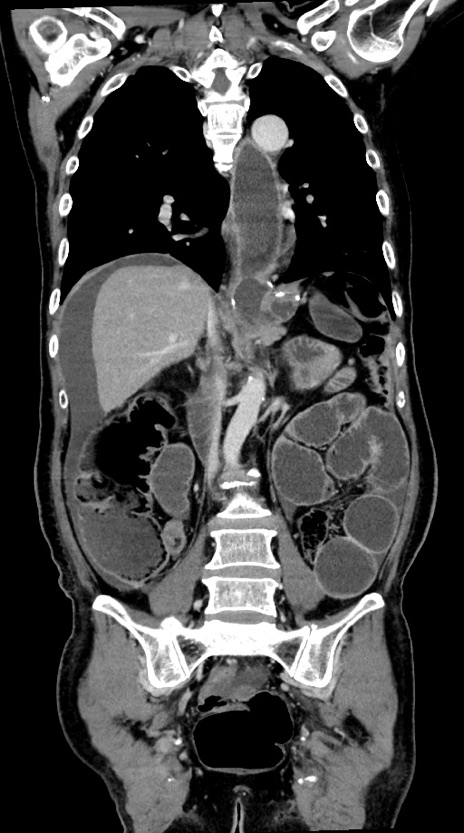

症例28(冠状断像)

【症例】60歳代男性

【主訴】嘔吐

【現病歴】胃癌にて胃全摘後。食思不振が悪化し、夜中に嘔吐することがある。

【既往歴】胃癌、胃全摘、脾摘、胆摘後

【データ】WBC 5900、CRP 10.56